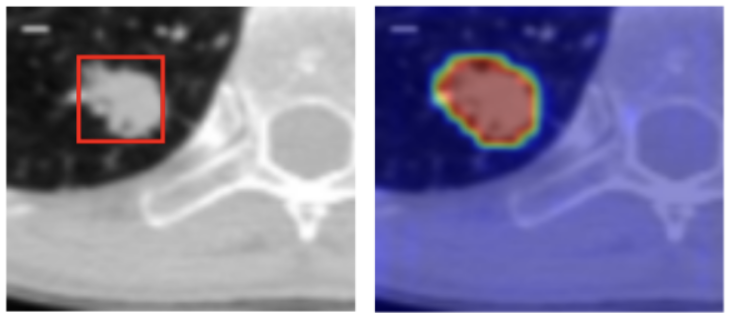

We generate x^*, which only requires slight modification within the area m (see the bottom right of the image). This indicates that f "understands" where in the image the malignant nodule is present. | You: Exactly! And how can you change it to a nine? Paul: I can add a line at the top to make it a nine! You: That's correct, you got it! |

This not only ensures that the model classifies the images correctly, but also that it pays attention to the right part of the image. We can see this here:

Thus we've managed to enforce causal alignment in our classifier f.